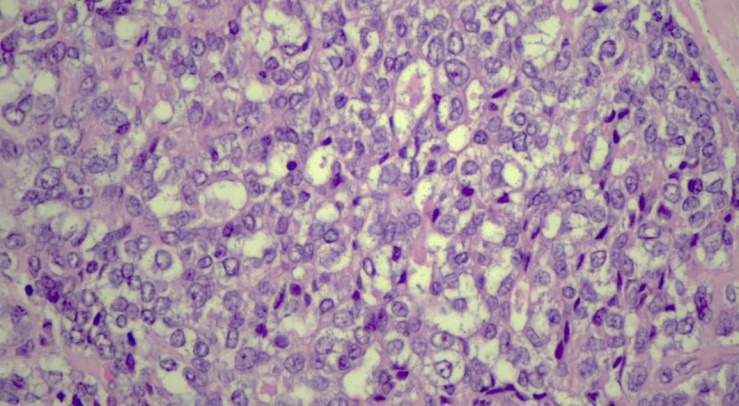

Hepatoblastoma is a tumor that arises from embryonic parenchymal liver cells, with an annual incidence of 1.2 cases per 1 million people. This disease accounts for about 79% of all liver tumors in children. According to statistics, 90% of all cases of hepatoblastomas occur in children under the age of 4 years [1]. Hepatoblastoma usually has a monofocus character, affecting more often the right lobe of the liver. A slightly higher prevalence is observed among boys. The tumor is divided into epithelial type hepatoblastoma and mixed epithelial/mesenchymal type [2]. Hepatoblastoma is usually manifested by bloating, weight loss and lag in physical development, and may be accompanied by jaundice and fever. At the same time, a high level of alpha-fetoprotein (AFP) in the blood serum is the main diagnostic and prognostic marker. The tumor increases in size quite rapidly, respectively, if the patient is left untreated, he will suffer death as a result of bleeding, liver failure and distant metastases [3]. The following is a description of a clinical case of a 5-year-old child who was taken to the hospital with bloating and abdominal pain. After an X-ray examination, a liver abscess was diagnosed, while histopathology showed that we are actually dealing with a hepatoblastoma.A clinical case. A 4-year-old girl was taken to the emergency department with complaints of an acute stomach and pain in the navel area during the day. Ultrasound examination of the abdominal cavity revealed a heterogeneous tumor-like formation measuring 3.5× 2.3× 2.0 cm. The formation was localized in the VI and VII segments of the liver. A site with calcifications was identified in the tumor lesion. There are separate areas of vascularization on color Dopplerography. Examination using CT with contrast enhancement (CECT) showed a heterogeneous formation without clear boundaries with cavities and outpouring of contrast agent into the VI segment of the liver, as well as hemorrhagic effusion in the abdominal cavity. An urgent laparotomy with tumor resection was performed. Alpha-fetoprotein (AFP) level control showed 55,000 IU/ml.Histopathology. Macroscopic description: a 4.7× 3.1× 2.2 cm fragment of the liver, subcapsularly dissected with a 3.5× 2.3 cm tumor with clear boundaries in the capsule, located directly at the edge of one of the edges of the resection (Fig. 1). The tumor is brownish-white in color with foci of hemorrhages. Microscopic examination shows an encapsulated liver tumor consisting of two lobes. Hepatoblastoma: description of a clinical case. cell types: a) small tumor cells with rounded and oval nuclei, sparse cytoplasm and pronounced nucleoli. These cells were arranged in strands and layers, resembling embryonic liver tissue; b) round and oval cells with a moderate amount of eosinophilic cytoplasm, grouped in the form of trabeculae and chains, similar to fetal liver (Fig. 1,2). | Figure 1. Hepatoblastoma site with fetal component. Increase .x200. H&E |